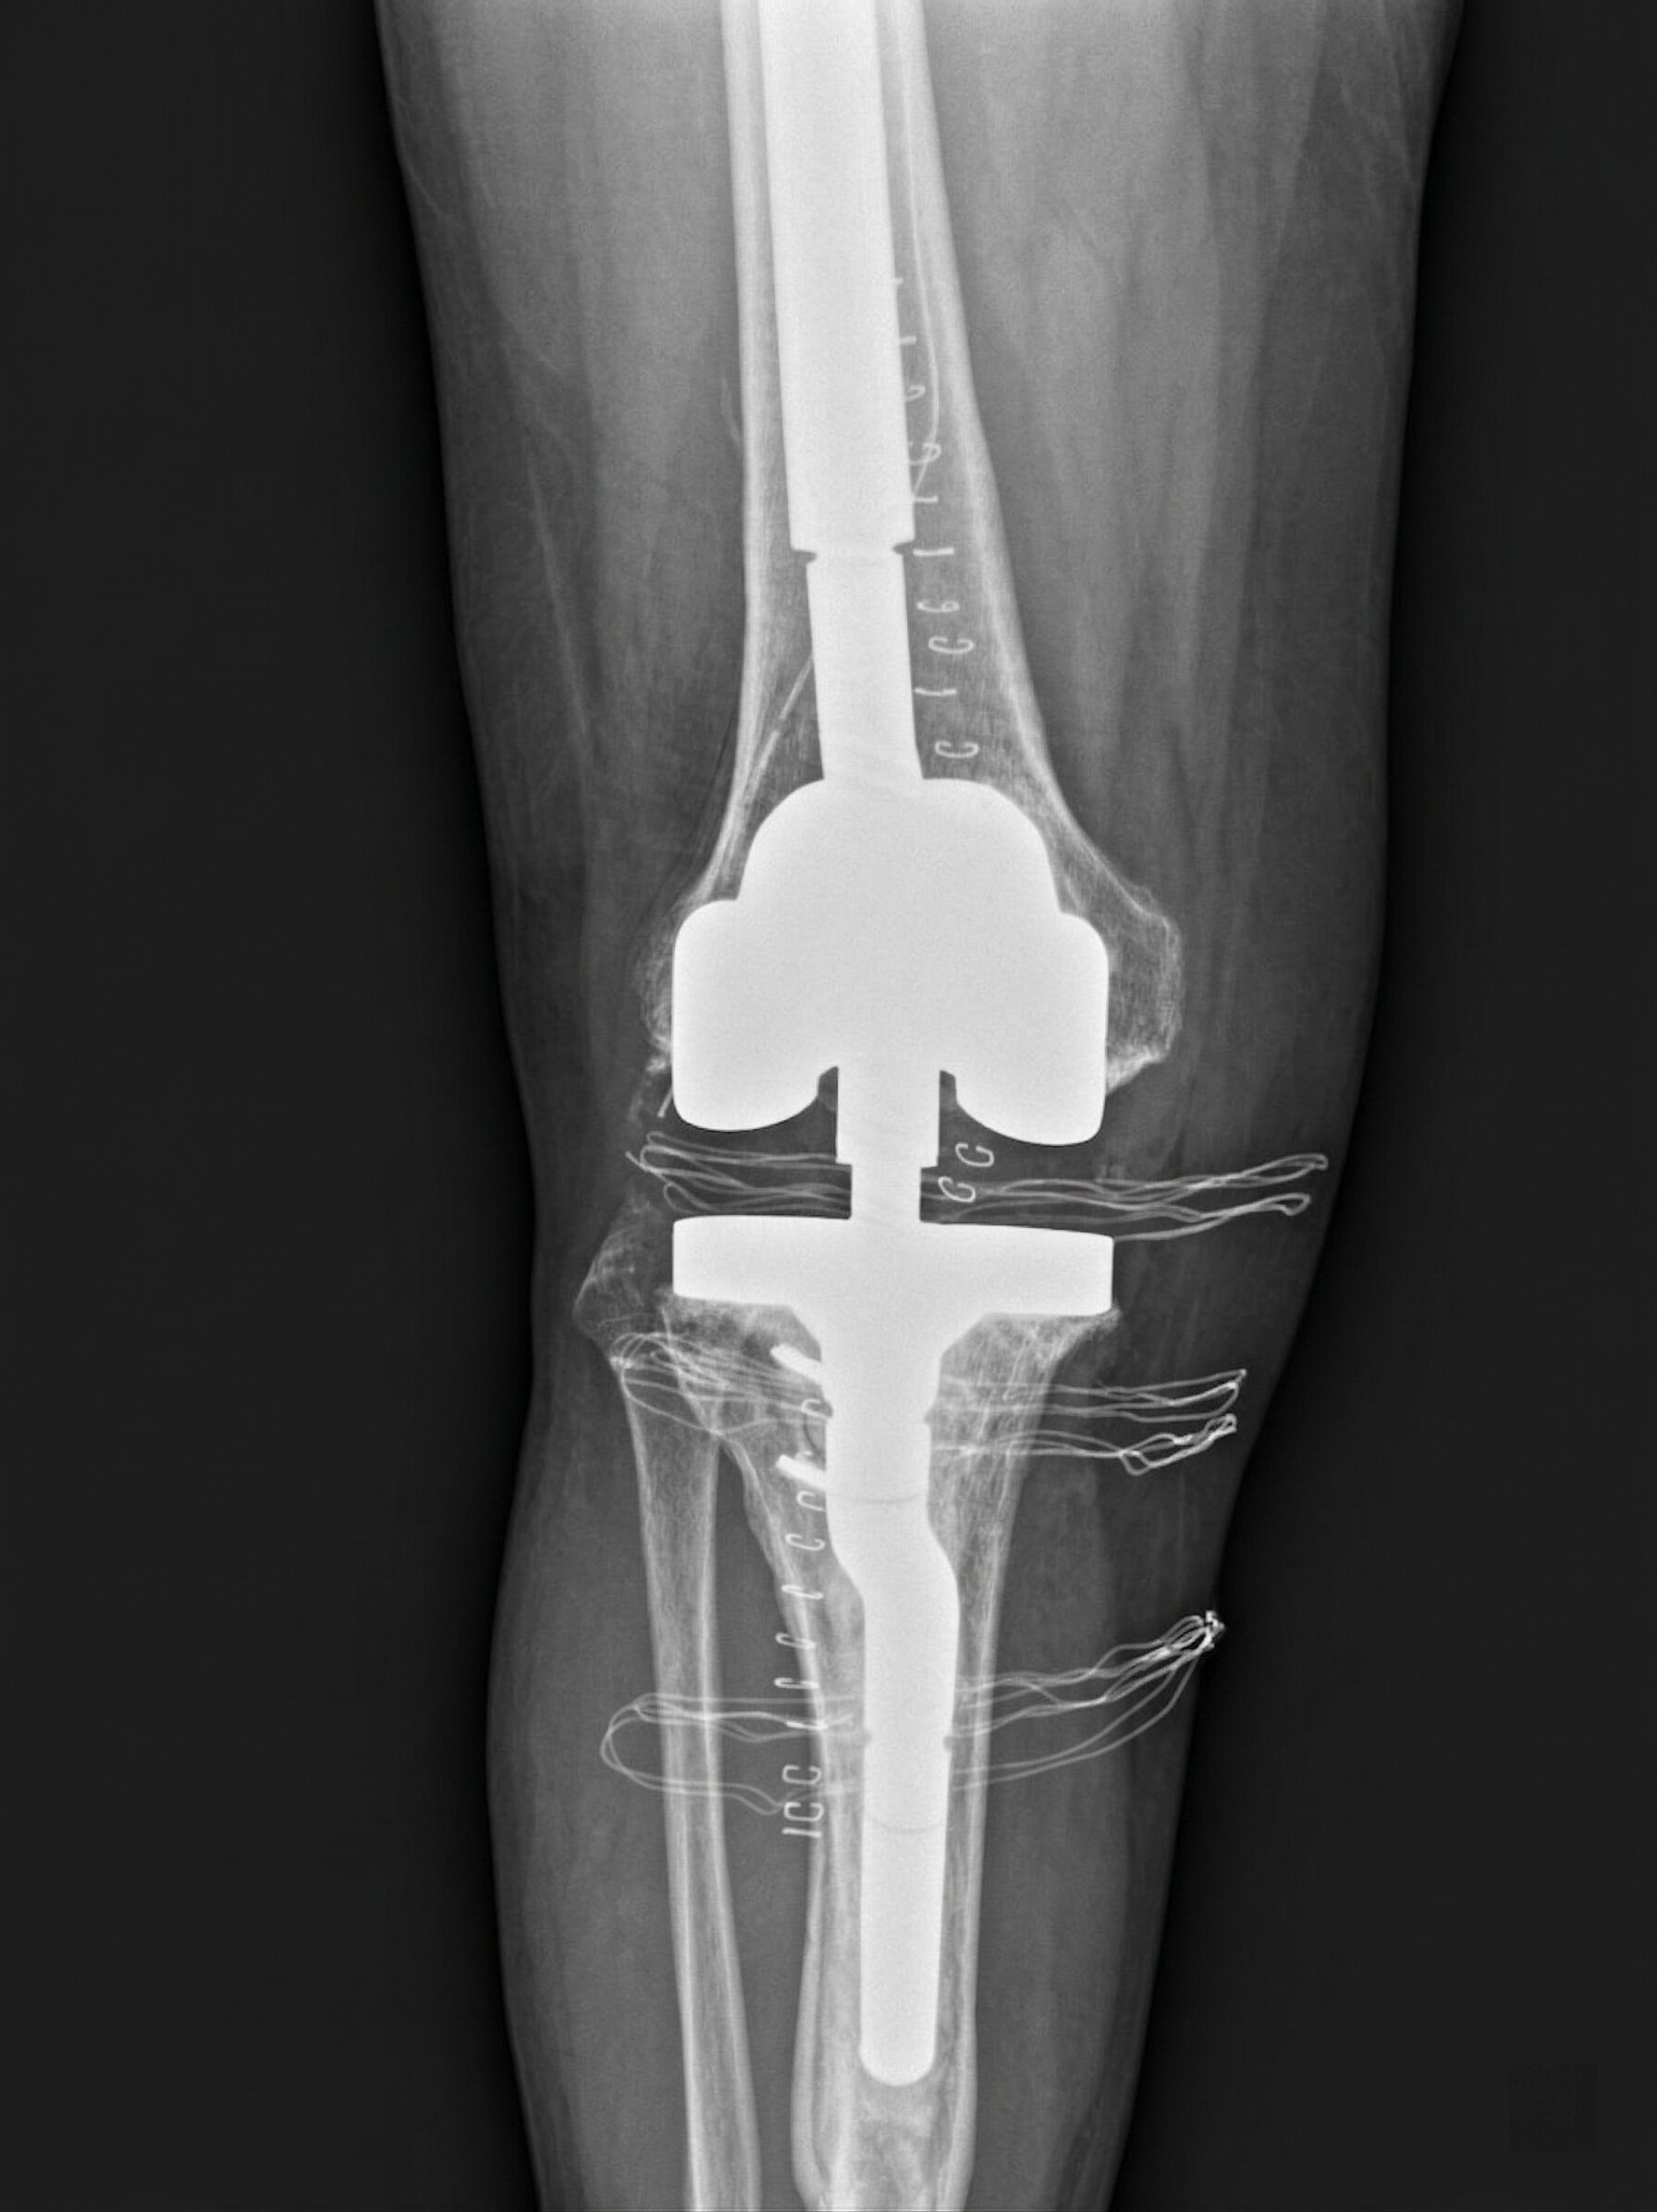

Fallimenti Meccanici: Revisione

Si verificano quando una protesi si usura, si mobilizza o perde funzione.

Il trattamento è chirurgico con revisione dell’impianto.